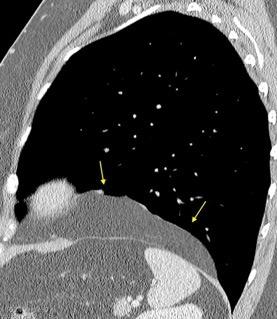

T. mixto de células germinales del testículo izquierdo

Nódulos pulmonares múltiples. (flechas verdes). Masas paratraqueales. (flechas amarillas). Dudoso ensanchamiento retrocrural (flechas negras). sigue….

Ttawfik A et al. Trans-diaphragmatic Pathologies: Anatomical Background and Spread of Disease on cross-sectional Imaging. Current Problems in Diagnostic Radiology. 2021.

T. mixto de células germinales del testículo

izquierdo Metástasis pulmonares. (flechas verdes). Ganglios paratraqueales. (flechas amarillas). Ganglios retroperitoneales (flechas negras)

Tawfik A et al. Trans-diaphragmatic Pathologies: Anatomical Background and Spread of Disease on cross-sectional Imaging. Current Problems in Diagnostic Radiology. 2021.